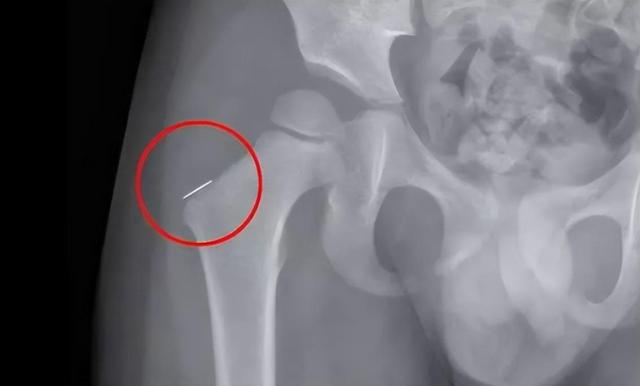

Sự việc chỉ được phát hiện sau khi họ Dương đã rời khỏi nhà của vợ chồng anh Trương. Vì con trai liên tục khóc lớn, vợ chồng anh đưa đi khám thì không tìm ra nguyên do. Mãi sau nhiều lần kiểm tra, các bác sĩ mới phát hiện trong người cậu bé có 2 mảnh kim loại gỉ sét dài 3cm. Một trong số đó nằm ở vị trí nguy hiểm, thậm chí đã ghim vào xương. Nếu phẫu thuật không cẩn thận sẽ chạm vào dây thần kinh và động mạch, nguy hiểm đến tính mạng. Vợ chồng anh Trương nghe tới đây không khỏi điếng người. Rất may mắn là ca phẫu thuật sau đó đã diễn ra thành công.